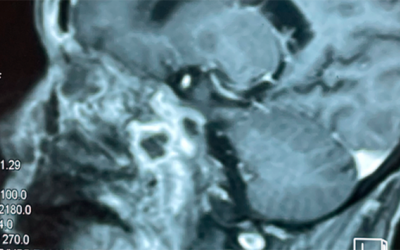

Chào chuyên gia! Tôi bị hở van tim và đã thay van tim được 2 năm nay. Nhưng gần đây, tôi thấy người mệt mỏi và khó thở nhiều hơn. Xin hỏi chuyên gia tôi nên điều trị ra sao? (N.V.A., Hạ Long)